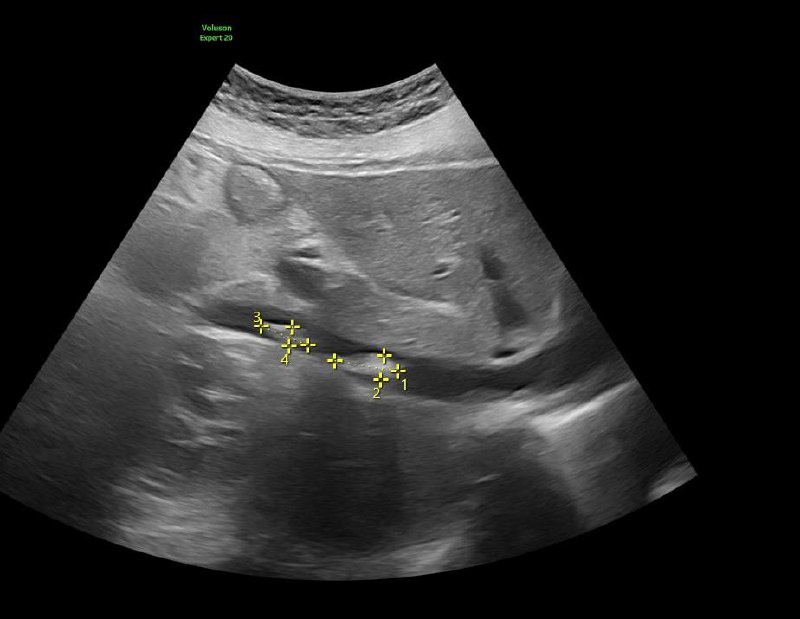

Когда ты не узист, а Врач ультразвуковой диагностики ⠀ ✅ В очередной раз нашел то, о чем не просили… ⠀ ✅ Две недели назад боли в животе, одышка ⠀ ✅ Предположительный диагноз - панкреатит и гастрит. Две недели лечения - без эффекта ⠀ ✅ Обратилась в нашу клинику для проведения УЗИ органов брюшной полости. Поджелудочная железа выглядит идеально ⠀ ✅ Учитывая жалобы на одышку И ДРУГИЕ СИМПТОМЫ, поставил датчик на область сердца. Моё заключение: тромбоз нижней полой вены, гидроперикард ⠀ ✅ Госпитализирована в профильную клинику, ведется лечение ⠀ ✅ НЕ ВСЕГДА НУЖНО НАЧИНАТЬ С УЗИ. ОБРАТИВШИСЬ К ТЕРАПЕВТУ И (ИЛИ) КАРДИОЛОГУ, ПАЦИЕНТА НАПРАВИЛИ БЫ НА ЭКГ И ЭХО-КС. ⠀ ✅ ТОЛЬКО ОЧНАЯ КОНСУЛЬТАЦИЯ СПЕЦИАЛИСТА ИЗБАВИТ ВАС ОТ НЕНУЖНЫХ ИССЛЕДОВАНИЙ ⠀ P.S. УЗИ сделано не кардиологическим датчиком и не на кардиологическом аппарате. ⠀ ✅ УЗИ сердца и сосудов у нас делает Юлия Сергеевна Шарпилова ⠀ ✅ Берегите себя ⠀ #саренко